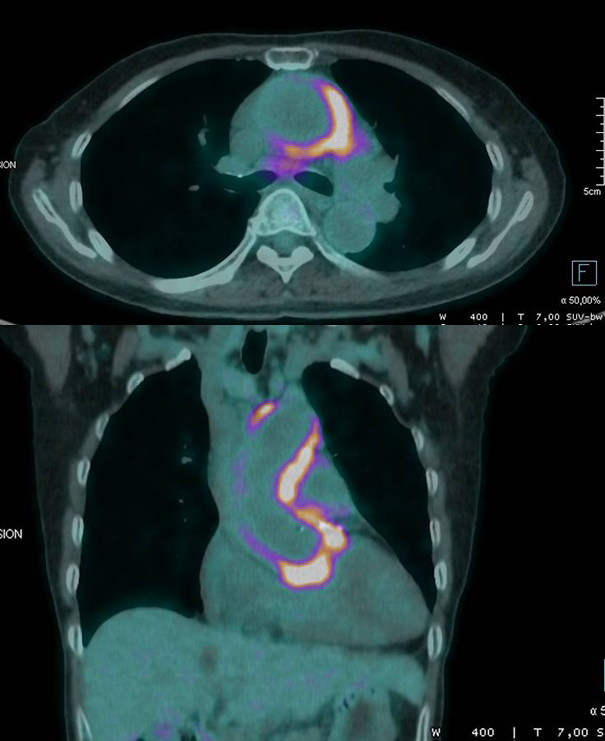

Vous recevez un patient de 65 ans adressé pour altération modérée de l’état général et syndrome inflammatoire prolongé. Il a eu plusieurs pancréatites au cours des dernières années. Il vient muni des résultats d’un TEP scanner dont voici les images clefs.

Il existe très clairement un épaississement hypermétabolique de l’aorte thoracique ascendante évocateur d’une aortite, qui fait partie du spectre des vascularites des gros vaisseaux.

Il faut rechercher des arguments pour une artérite à cellules géantes, une vascularite à ANCA (qui donne plus souvent une atteinte des petits vaisseaux, mais parfois aussi des aortites), une maladie associée aux IgG4 (surtout vu les pancréatites à répétition), et aussi bien sûr les aortites infectieuses.